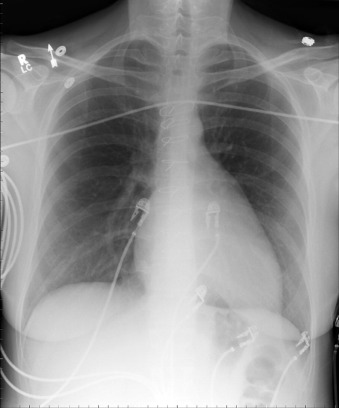

There is cardiomegaly with prominence of the right atrial contour, a small main pulmonary artery due to rotation of the heart due to Ebstein’s anomalies. The patient had previously undergone surgical repair of an associated atrial septal defect.